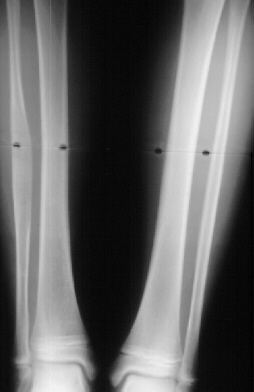

A 10 year old white female was evaluated in the orthopaedic clinic for leg length discrepancy. Her disease process has been characterized by early breast development at 3 years of age, menarche at the age of 6, and a pathologic subtrochanteric fracture after a trivial fall at age 8. She now complains of a limp and pain after long walks. The patient demonstrated a large pigmented lesion with irregular border located in the right upper back. There was a two centimeter leg length discrepancy by the block test.

The leg length discrepancy can be treated by distraction lengthening through an area of the femur not involved in the lesion.